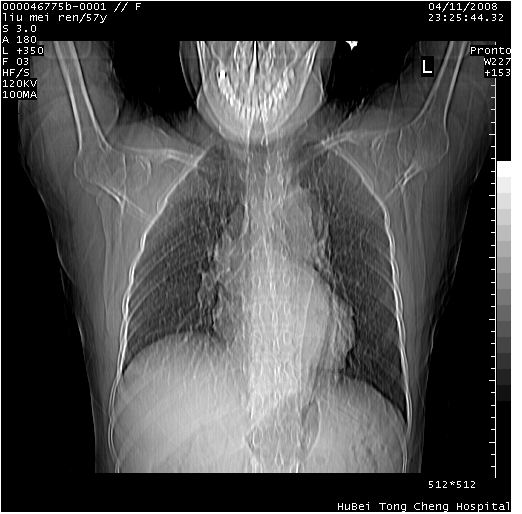

患者 女,57岁。因车祸受伤,其家属要求行“全身ct检查”。平素健康。

胸部ct轴位平扫(层厚10mm,螺距1.5,重建间隔10mm),图像如下: